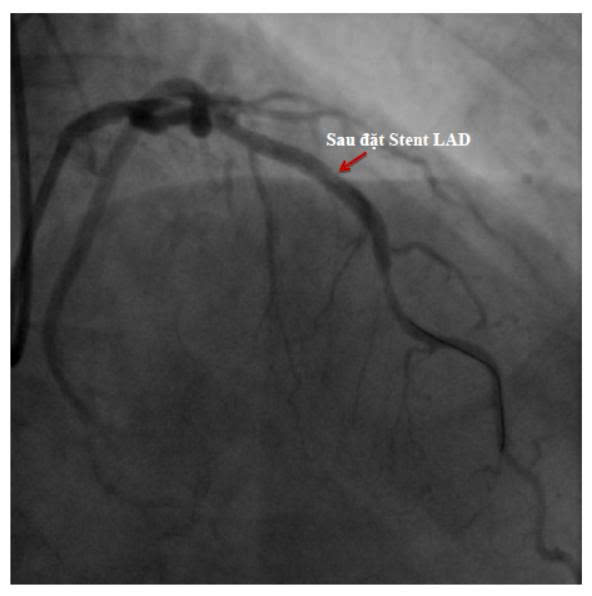

Tuy nhiên, khi kiểm tra chuyên sâu, bác sĩ phát hiện hẹp nặng động mạch vành LAD – nhánh mạch quan trọng nuôi tim.

👉 Với trường hợp này, đặt stent mạch vành kịp thời đã giúp tái thông dòng máu, giảm nguy cơ nhồi máu cơ tim và bảo vệ chức năng tim lâu dài.